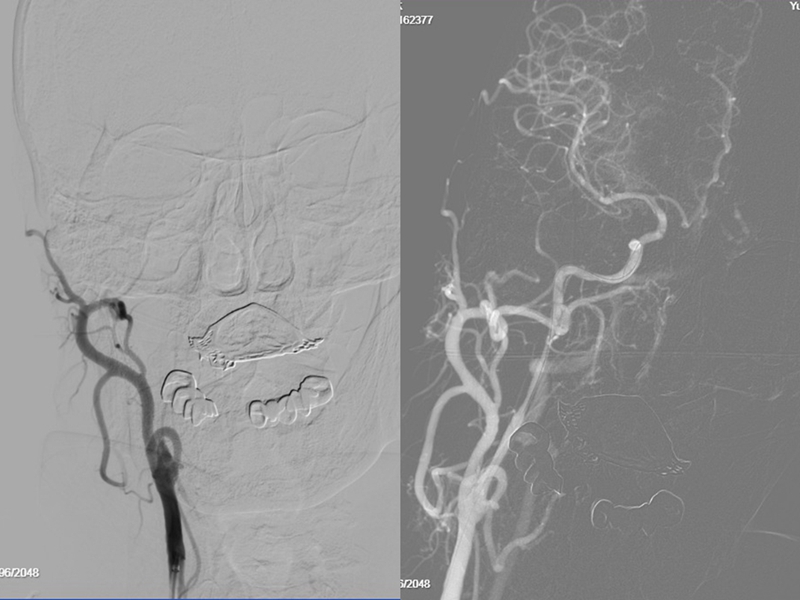

术中,通过脑血管造影发现,老人的右颈内动脉起始段完全闭塞,远端的大脑中动脉M1段被血栓完全堵塞,是极其复杂的串联病变。

危急时刻,曾怀文和高潮二人紧密配合,先实行球囊扩张技术开通右颈内动脉,继而快速取出颅内血栓,随后再次球囊扩张右颈内动脉并植入支架,最终成功恢复脑部血流。

术前 术后

病情重,术式复杂难度高,凭借丰富经验和娴熟技术,此次手术,脑卒中治疗的关键指标DPT时间(从患者到达医院到穿刺成功的时间?)仅为47分钟,远远快于标准时间120分钟!